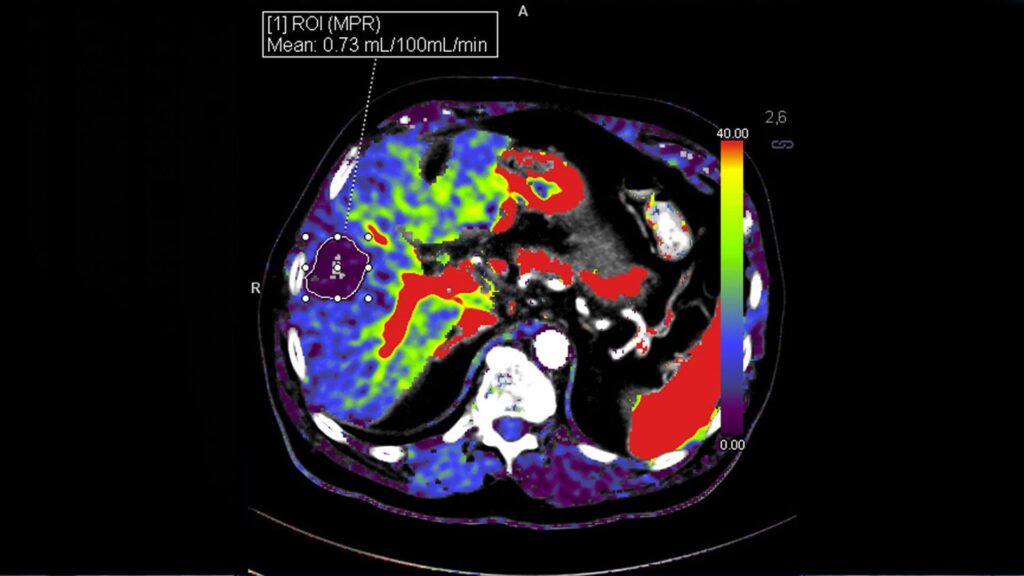

Nexaris Angio-CT is a hybrid interventional suite with Instant Fusion that seamlessly integrates Angio and CT images. Even wireless ultrasound images can be displayed side-by-side on the Large Display so that Angio, CT and ultrasound images are available at a single glance. This enables you to perform challenging multi-modality procedures and streamline workflows with the piece of mind every pioneer needs.